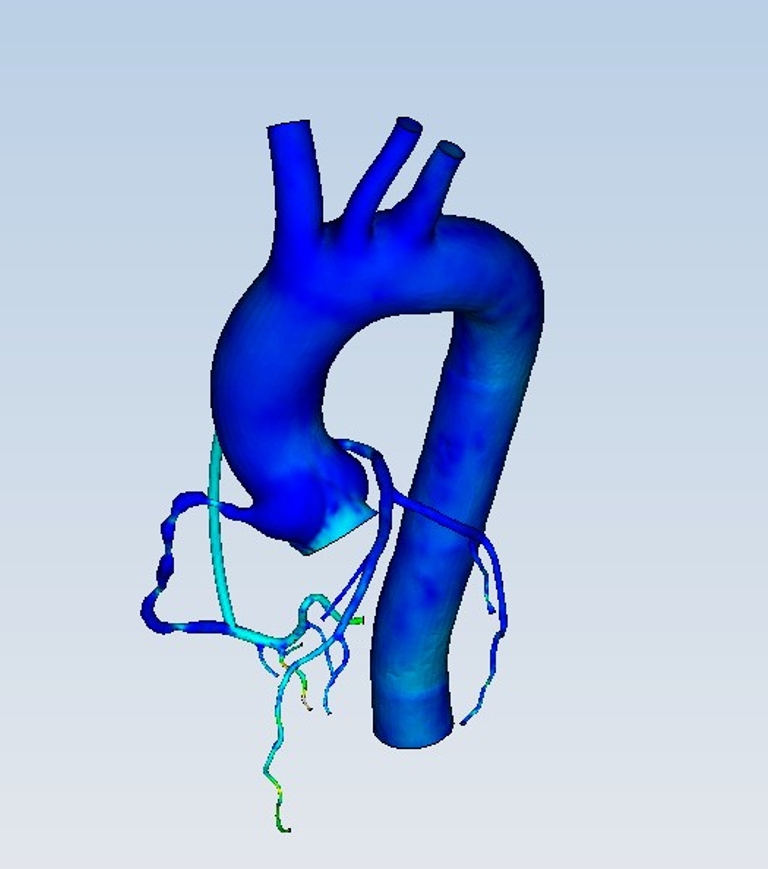

- 8 主动脉血流动力学仿真

流体 | 主动脉血流动力学仿真APP用于描述主动脉里的血流动力学情况。血液在主动脉里流动过程中,会根据血管形态改变流速与压力,沿途会有部分血液进入分支血管。主动脉血流动力学仿...

- 59 冠状动脉含主动脉根部血流动力学仿真

流体 | 冠状动脉含主动脉根部血流动力学仿真APP描述冠状动脉(含主动脉根部)内的血液流动情况。血液在冠状动脉里流动过程中,会根据血管形态改变流速与压力,从而影响冠状动脉上疾...